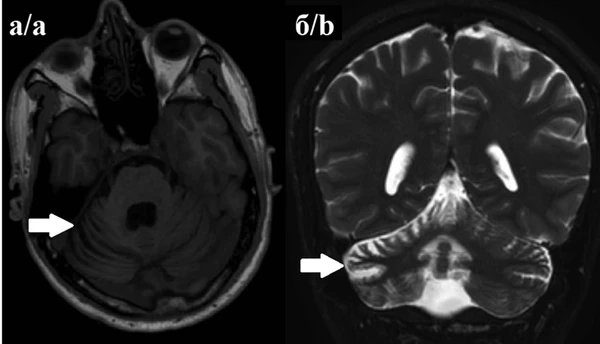

Магнитно-резонансная томография головного мозга: картина обычно остаётся нормальной на ранних стадиях, однако в ряду случаев может определяться атрофия мозжечка[6].